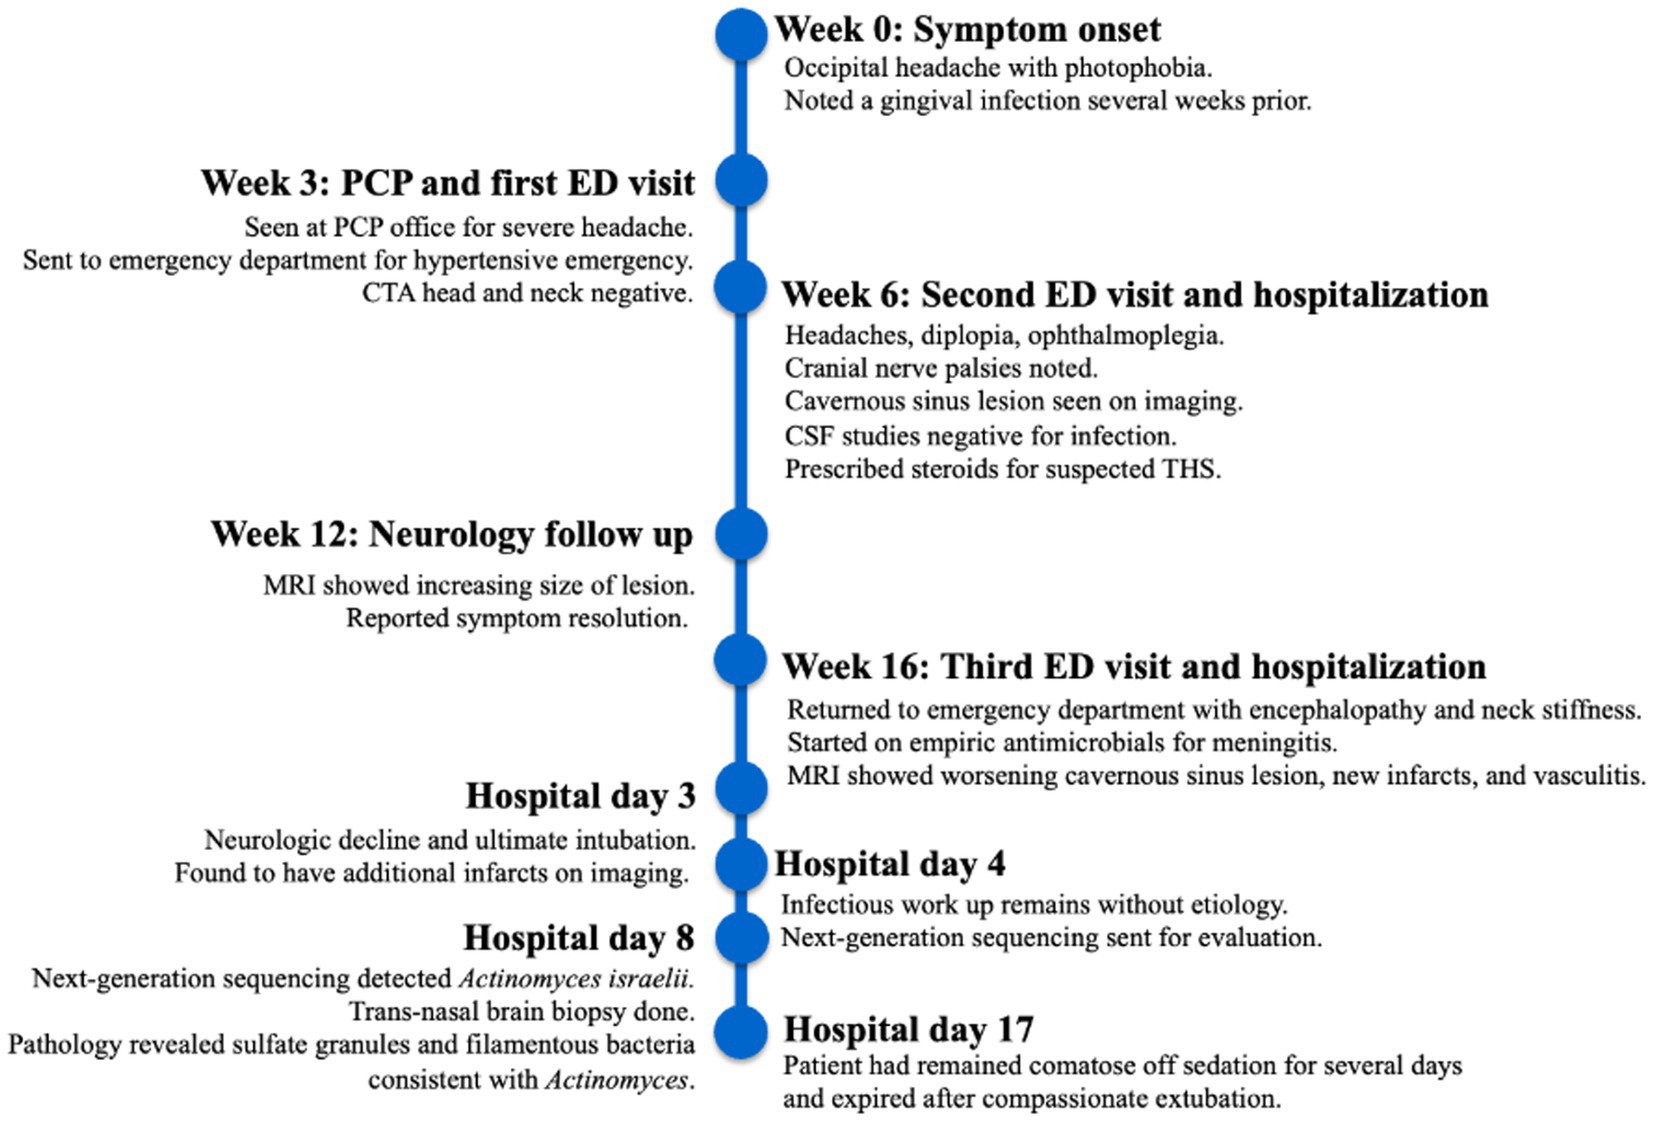

Furthermore, 6 weeks after his initial presentation, follow-up MRI revealed an increase in the size of the cavernous sinus lesion from 1.7 × 1.7 × 1.6 cm to 1.8 × 2.0 × 1.8 cm, demonstrating further extension of the lesion into the Meckel’s cave and along the trigeminal maxillary division, accompanied by further narrowing of the left ICA (Figure 1). He underwent a positron emission tomography (PET) scan to evaluate for other areas of malignancy/granulomatous disease, with the differential diagnoses being unchanged. The patient continued to experience headaches; however, cranial nerve III and VI palsies and diplopia had resolved.

Figure 1. MRI skull base T1 + C at 6-week follow-up with reported improvement of symptoms. (A) Interval increase in the cavernous sinus mass size with extension into the pituitary fossa. (B) Subtle enhancement along V2 on the left, suggesting infiltrative process(inlet). (C) Narrowing of the left ICA.